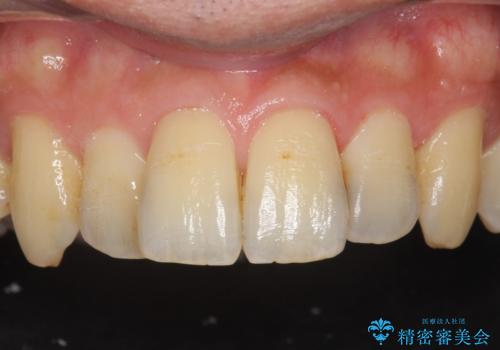

古い樹脂を除去してe-maxインレー

- 樹脂の材料での治療をセラミックに変えたいとの事で来院。

拡大鏡下で古い樹脂を除去し、虫歯がない事を確認してe-maxインレーで治療を行いました。